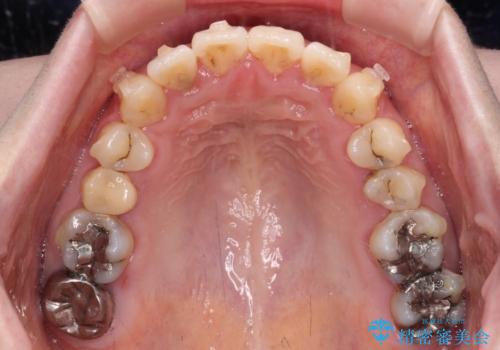

- 捻れた前歯が飛び出しており、口が閉じにくいとのことで来院された患者様です。

出っ歯というわけではないものの、前歯の捻転により口唇が押し出されている状態でした。

親知らずを抜去し、歯列全体を後方に移動させつつ、IPR(歯と歯の間を削る)でスペースを獲得し、インビザラインを用いて叢生を解消しながら前歯の突出を改善することとしました。

インビザラインは、患者様の協力無しには成立しない治療ですが、しっかりと装着時間を遵守してくださり、1年弱で治療を終えることができました。